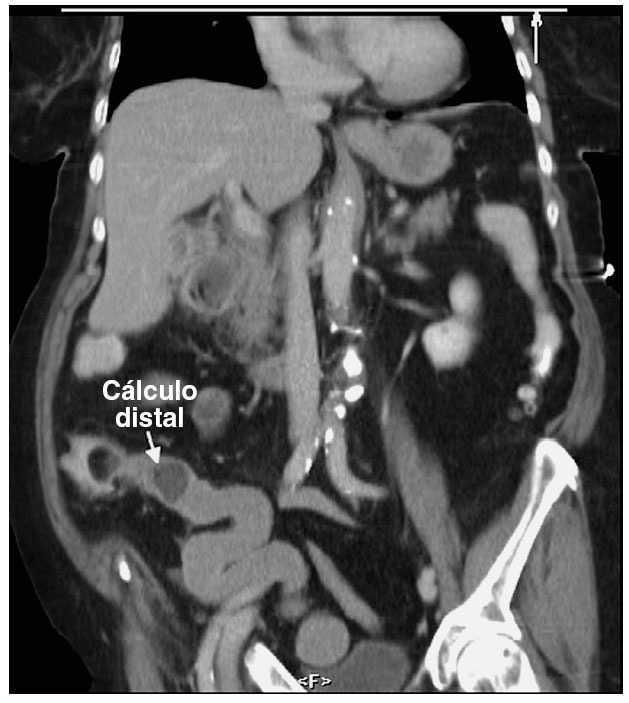

Paciente de 92 años que ingresó por clínica de vómitos de repetición y deshidratación. Al examen presentaba distensión abdominal y dolor en hipocondrio derecho. En la radiografía de abdomen se evidenció distensión gástrica. Se practicó tomografía computarizada que objetivó distensión gástrica, aerobilia, fístula colecistoduodenal con cálculo duodenal (fig. 1) y otra imagen de cálculo en íleon distal (fig. 2). Se decidió realizar laparotomía, con el hallazgo de plastrón que se disecó, y se practicó colecistectomía, duodenotomía, extracción del cálculo impactado en el duodeno y duodenorrafia. Se exploró el resto del intestino sin hallar el cálculo y al tacto rectal se lo objetivó desmenuzado. El postoperatorio cursó sin incidencias.

Fig. 2.

Diagnóstico: Síndrome de Bouveret.